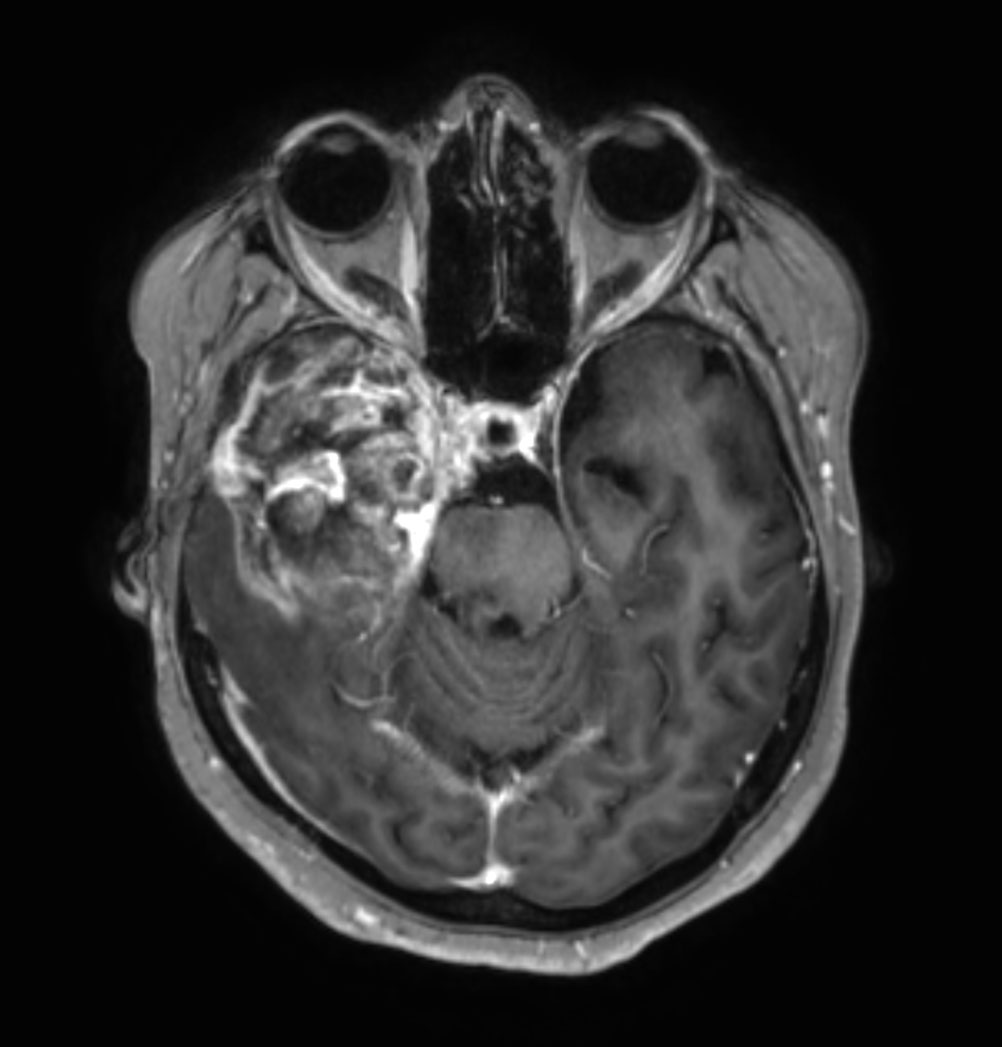

Brain astrocytoma post radiotherapy, incl. 3D APT

Patient with a history of astrocytoma. MRI scan requested post radiotherapy treatment. Diagnosis: Recurrent neoplastic disease.

Axial 3D APT